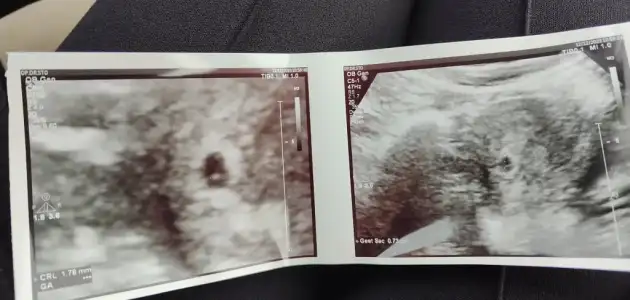

Canım kalp atışı 5+5 mi yazayım?Yaş 33

İkinci hamilelik

Sat 1 kasım

5+1 kese göründü

5+5 bebek göründü

Beklenen doğum tarihi 7 Ağustos

İzmir